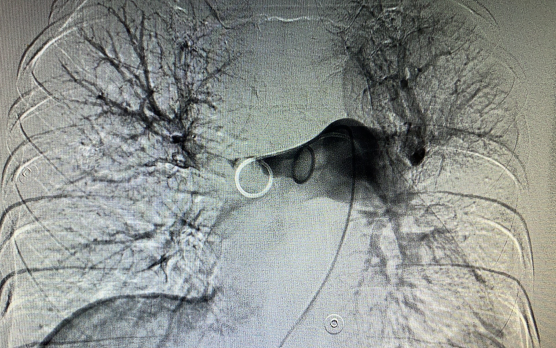

2021年1月4号晚上19点16分,患者张某,突发胸闷憋喘,我院心内科、胸外科、呼吸内科、重症监护室、介入医学科联合会诊考虑肺栓塞可能性大,急查肺动脉CTA 明确诊断。考虑患者病情重,随时有猝死的可能,介入医学科付信军主任决定急诊行下腔静脉滤器植入+肺动脉置管溶栓术抢救患者生命,给患者生的希望,术后积极溶栓抗凝治疗,现患者已较前明显好转。下图为术前术后肺动脉造影对比图: